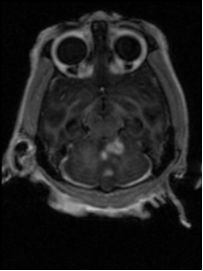

MRI Image

The bright spots indicate MS-like lesion in the monkey's brain.